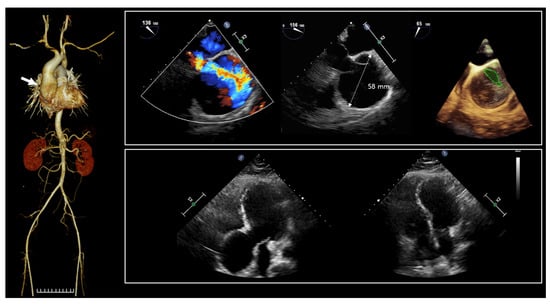

The proband (II-1 in Figure 1a), a 36-year-old man, was admitted to the hospital due to dyspnea. Since birth, he has experienced hypotonia, blindness in both eyes, and hearing impairment. He was the first child of nonconsanguineous parents, and the pregnancy was uneventful at 38 weeks of gestation. Family history was unremarkable. His growth percentiles were within normal ranges at birth. In the early infant period, he showed generalized hypotonia, and growth motor slowly improved in childhood. Throughout his early development, he displayed global developmental delay, eventually reaching borderline intellectual disability (ID) with an intellectual quotient of 75 using the Wechsler Adult Intelligence Scale. As a result, he attended a specialized school for handicapped children due to total blindness and a borderline IQ. He did not live independently and required assistance for daily living. Moreover, he encountered challenges in obtaining employment. Snoring has been a consistent issue since childhood, leading to a diagnosis of obstructive sleep apnea based on polysomnogram results. His body mass index was 28 kg/m2 (90th percentile), which corresponds to overweight. Upon admission, vital signs were stable, with blood pressure at 110/60 mmHg, heart rate at 60 beats per minute, respiratory rate at 16 beats per minute, and body temperature at 36.6 °C. Physical examination revealed several abnormalities, including short stature (153.7 cm, below the 3rd percentile), a short neck, pectus carinatum, humped back, excess nuchal skin, facial dysmorphism (swollen eyelids, blepharophimosis, wide nasal bridge, a high forehead), vertebral anomaly, arachnodactyly, and edema in both lower extremities (Figure 1b). He was diagnosed with almost total blindness with nonlight perception at around 2 years old, and an ophthalmologic examination revealed optic atrophy (Figure 1c). Brain magnetic resonance imaging indicated diffuse cerebral atrophy, and cervical computed tomography scan revealed disc bulging with spondylosis (Figure 1d). Laboratory findings showed an elevated N-terminal prohormone of brain natriuretic peptide (248.10 pg/mL; reference range, 42.5 to 106.4), while highly sensitive troponin T (0.004 ng/mL; reference range, <0.014) and creatine kinase-MB (0.90 ng/mL; reference range, <2.2) were within normal limits. Nonspecific findings were observed in complete blood count, blood chemistry, metabolic screening, and urinalysis. Two years prior to admission, a transthoracic echocardiogram (TTE) conducted at the outpatient setting displayed normal left ventricular systolic function with an ejection fraction (EF) of 59%, and the ascending aorta measured 45 mm in diameter. Due to poor echo windows caused by pectus carinatum, assessment of the aortic valve and aortic root was inconclusive. A chest aorta computer tomography scan (CT) performed during the present admission revealed marked aneurysmal dilatation, approximately 5.8 cm from the aortic annulus to the proximal ascending aorta (Figure 2). A three-dimensional transesophageal echocardiogram exhibited aortic root aneurysm and bicuspid aortic valve (sinus of Valsalva = 58 mm) (upper panel in Figure 2). TTE during the current admission showed dilatation of the aortic root and right ventricular dilatation (lower panel in Figure 2).

Figure 2. Computed tomography scan of the chest aorta revealed aneurysmal dilatation of about 5.8 cm from the aortic annulus to the proximal ascending aorta (arrow). Color doppler echocardiography of aortic root aneurysm; red and blue represents flow towards and away from the transducer, respectively. A 3-dimensional transesophageal echocardiogram shows aortic root aneurysm and bicuspid AV (sinus of Valsalva = 58 mm) (upper panel). Bicuspid AV is represented by green outline. Transthoracic echocardiography at present admission showed dilatation of aortic root and RV dilatation (lower panel).